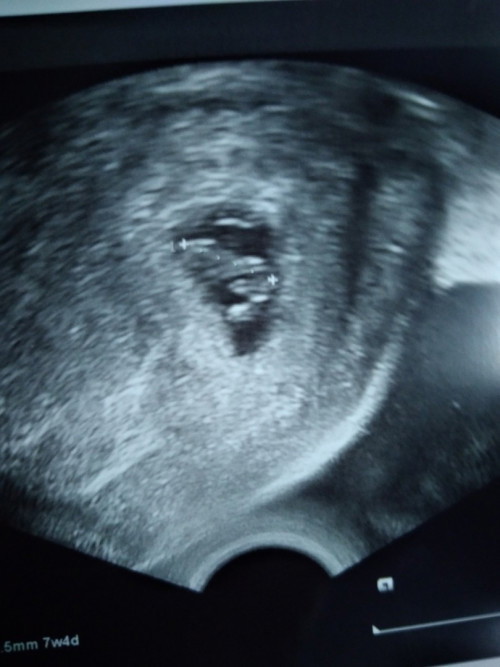

7w4d